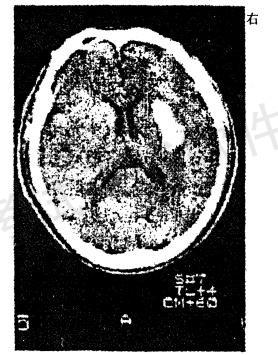

男性,56岁。高血压患者。旅游登山中突然左侧 肢体发麻、乏力。急送医院,摄头颅CT片如图

最可能的诊断是A.脑出血

B.脑血栓形成

C.蛛网膜下...